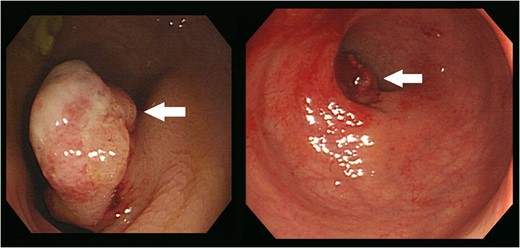

Colonoscopy revealed an ~2.5 cm-sized pedunculated lesion with surface ulceration at 10 cm from the anal verge (arrows).